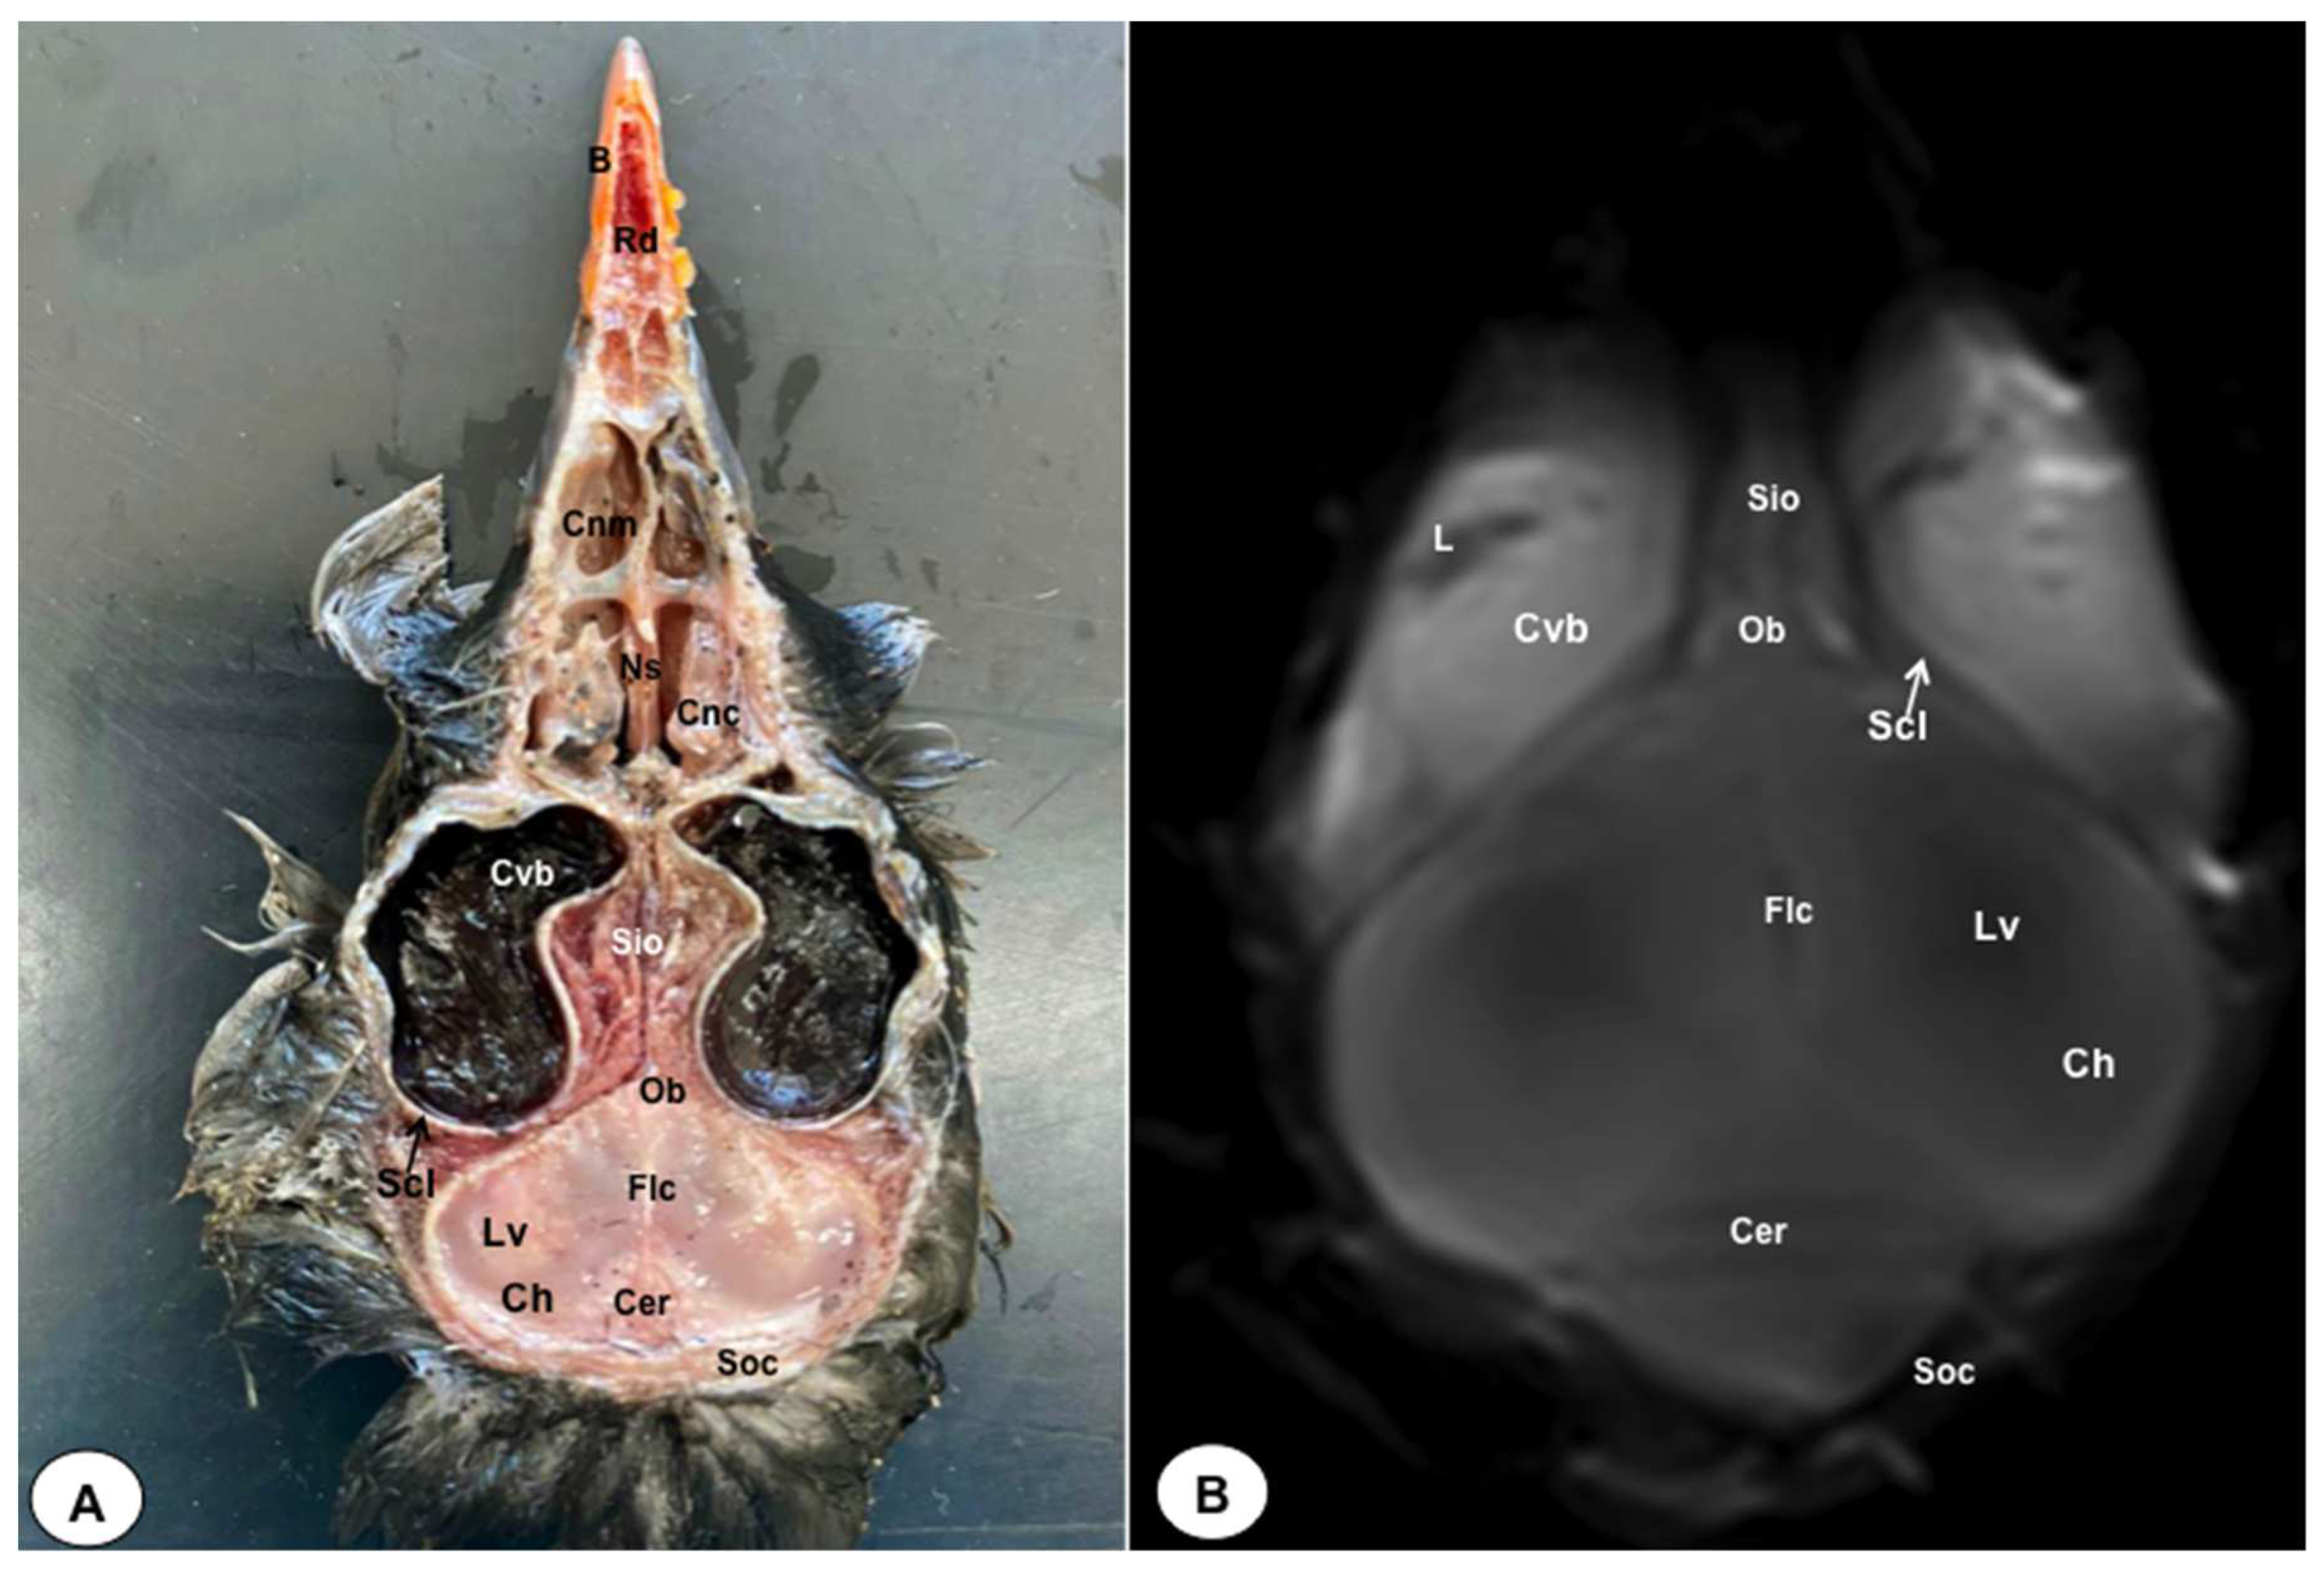

Figure 7. Dorsal cross-section (A) and T2W MR (B) images of the atlantic puffin head at the level of the nasal cavity corresponding to line VI inFigure 1. B: beak; Rd: rostral diverticulum; Cnm: Concha nasalis media; Cnc: concha nasalis caudalis; Ns: nasal septum; Cvb: camera vitrea bulbi; Sio: septum interorbitalis; Ob: olfatory bulb; Flc: fissura longitudinalis cerebri; Ch: cerebral hemisphere: Lv: lateral ventricle; Cer: cerebellum; Scl: sclera; Soc: Os supraoccipitale.